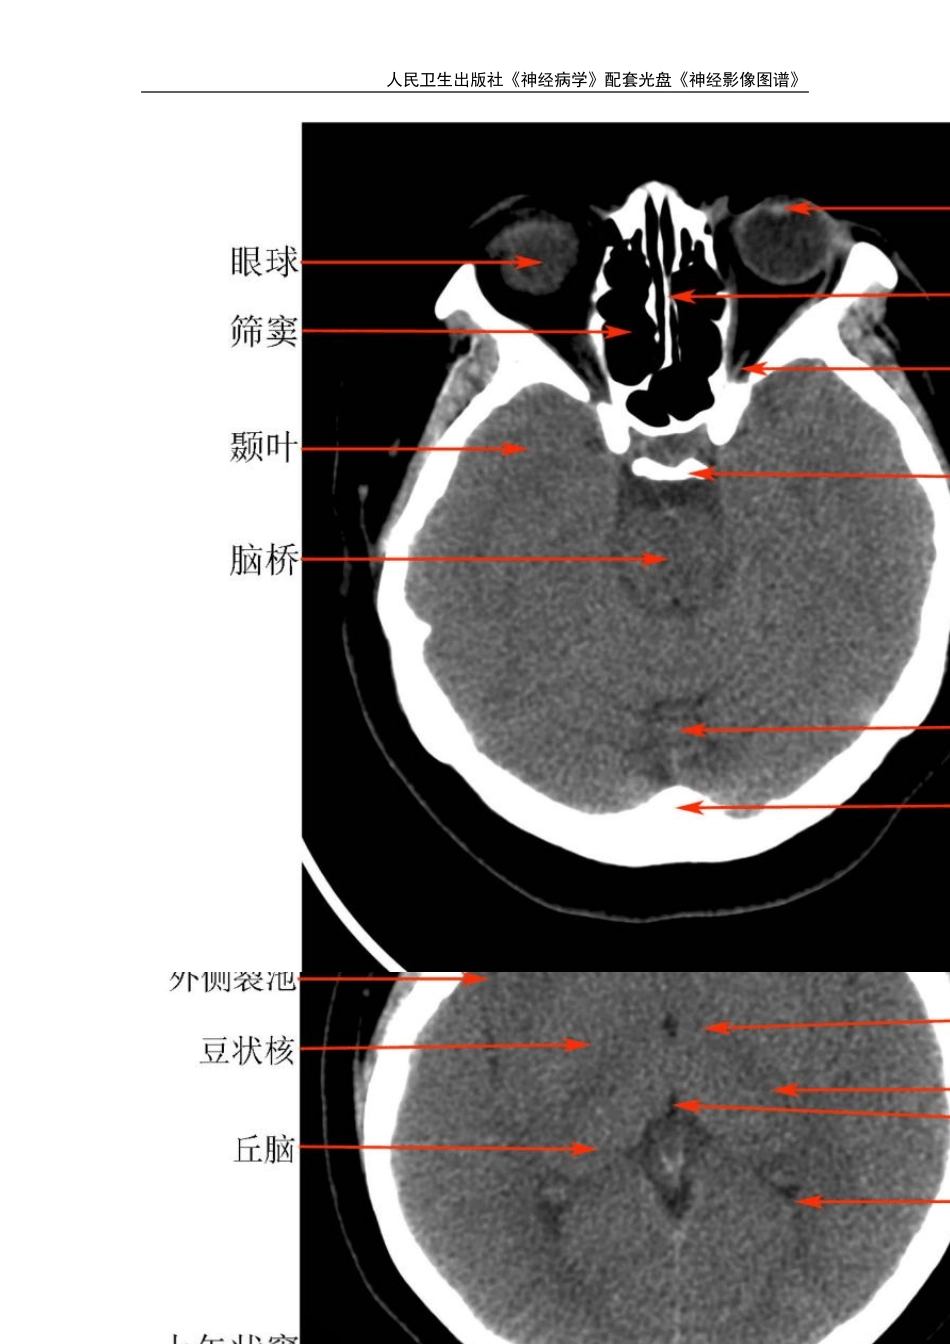

人民卫生出版社《神经病学》配套光盘《神经影像图谱》 人民卫生出版社《神经病学》配套光盘《神经影像图谱》 第一章 正常头颅影像学 第一节 正常头 CT 人民卫生出版社《神经病学》配套光盘《神经影像图谱》 人民卫生出版社《神经病学》配套光盘《神经影像图谱》 人民卫生出版社《神经病学》配套光盘《神经影像图谱》 第二节 正常头 MR 人民卫生出版社《神经病学》配套光盘《神经影像图谱》 人民卫生出版社《神经病学》配套光盘《神经影像图谱》 人民卫生出版社《神经病学》配套光盘《神经影像图谱》 人民卫生出版社《神经病学》配套光盘《神经影像图谱》 人民卫生出版社《神经病学》配套光盘《神经影像图谱》 人民卫生出版社《神经病学》配套光盘《神经影像图谱》 人民卫生出版社《神经病学》配套光盘《神经影像图谱》 第三节 正常 CTA 、人民卫生出版社《神经病学》配套光盘《神经影像图谱》 人民卫生出版社《神经病学》配套光盘《神经影像图谱》 第四节 正常 MRA 人民卫生出版社《神经病学》配套光盘《神经影像图谱》 第二章 脑血管病 第一节 脑梗塞 左侧额颞叶、基底节区超急性期脑梗死,发病 2 小时,T1WI、T2WI 及 flair 像未见异常信号,DWI 见高信号,ADC 图为低信号,MRA 示左侧大脑中动脉闭塞,右侧大脑中动脉狭窄。 人民卫生出版社《神经病学》配套光盘《神经影像图谱》 左侧基底节区急性期脑梗死,发病24 小时,T1WI 为稍低信号,T2WI 及flair 像为稍高信号,DWI 为高信号,MRA 示左侧大脑中动脉闭塞,此时头CT 未见异常改变。 人民卫生出版社《神经病学》配套光盘《神经影像图谱》 左侧基底节区亚急性期脑梗死,发病7 天,T1WI 为稍低信号,T2WI 及flair 像为高信号,DWI 为高信号,ADC 图为等信号,MRA 示左侧大脑中动脉闭塞。 人民卫生出版社《神经病学》配套光盘《神经影像图谱》 右侧基底节区多发腔隙性脑梗塞形成软化灶,周围见胶质细胞增生。 人民卫生出版社《神经病学》配套光盘《神经影像图谱》 皮层下动脉硬化性脑病,脑萎缩脑沟增宽加深脑室增大,双侧放射冠多发腔隙性脑梗塞部分已软化,双侧脑室周围对称性条带状异常信号。 人民卫生出版社《神经病学》配套光盘《神经影像图谱》 脑桥梗塞,发病3 天,T1WI 为稍低信号,T2WI 及flair 像为高信号,DWI 为高信号。 人民卫生出版社《神经病学》配套光盘《神经影像图谱》 右侧小脑梗塞,发病3 天,T1...